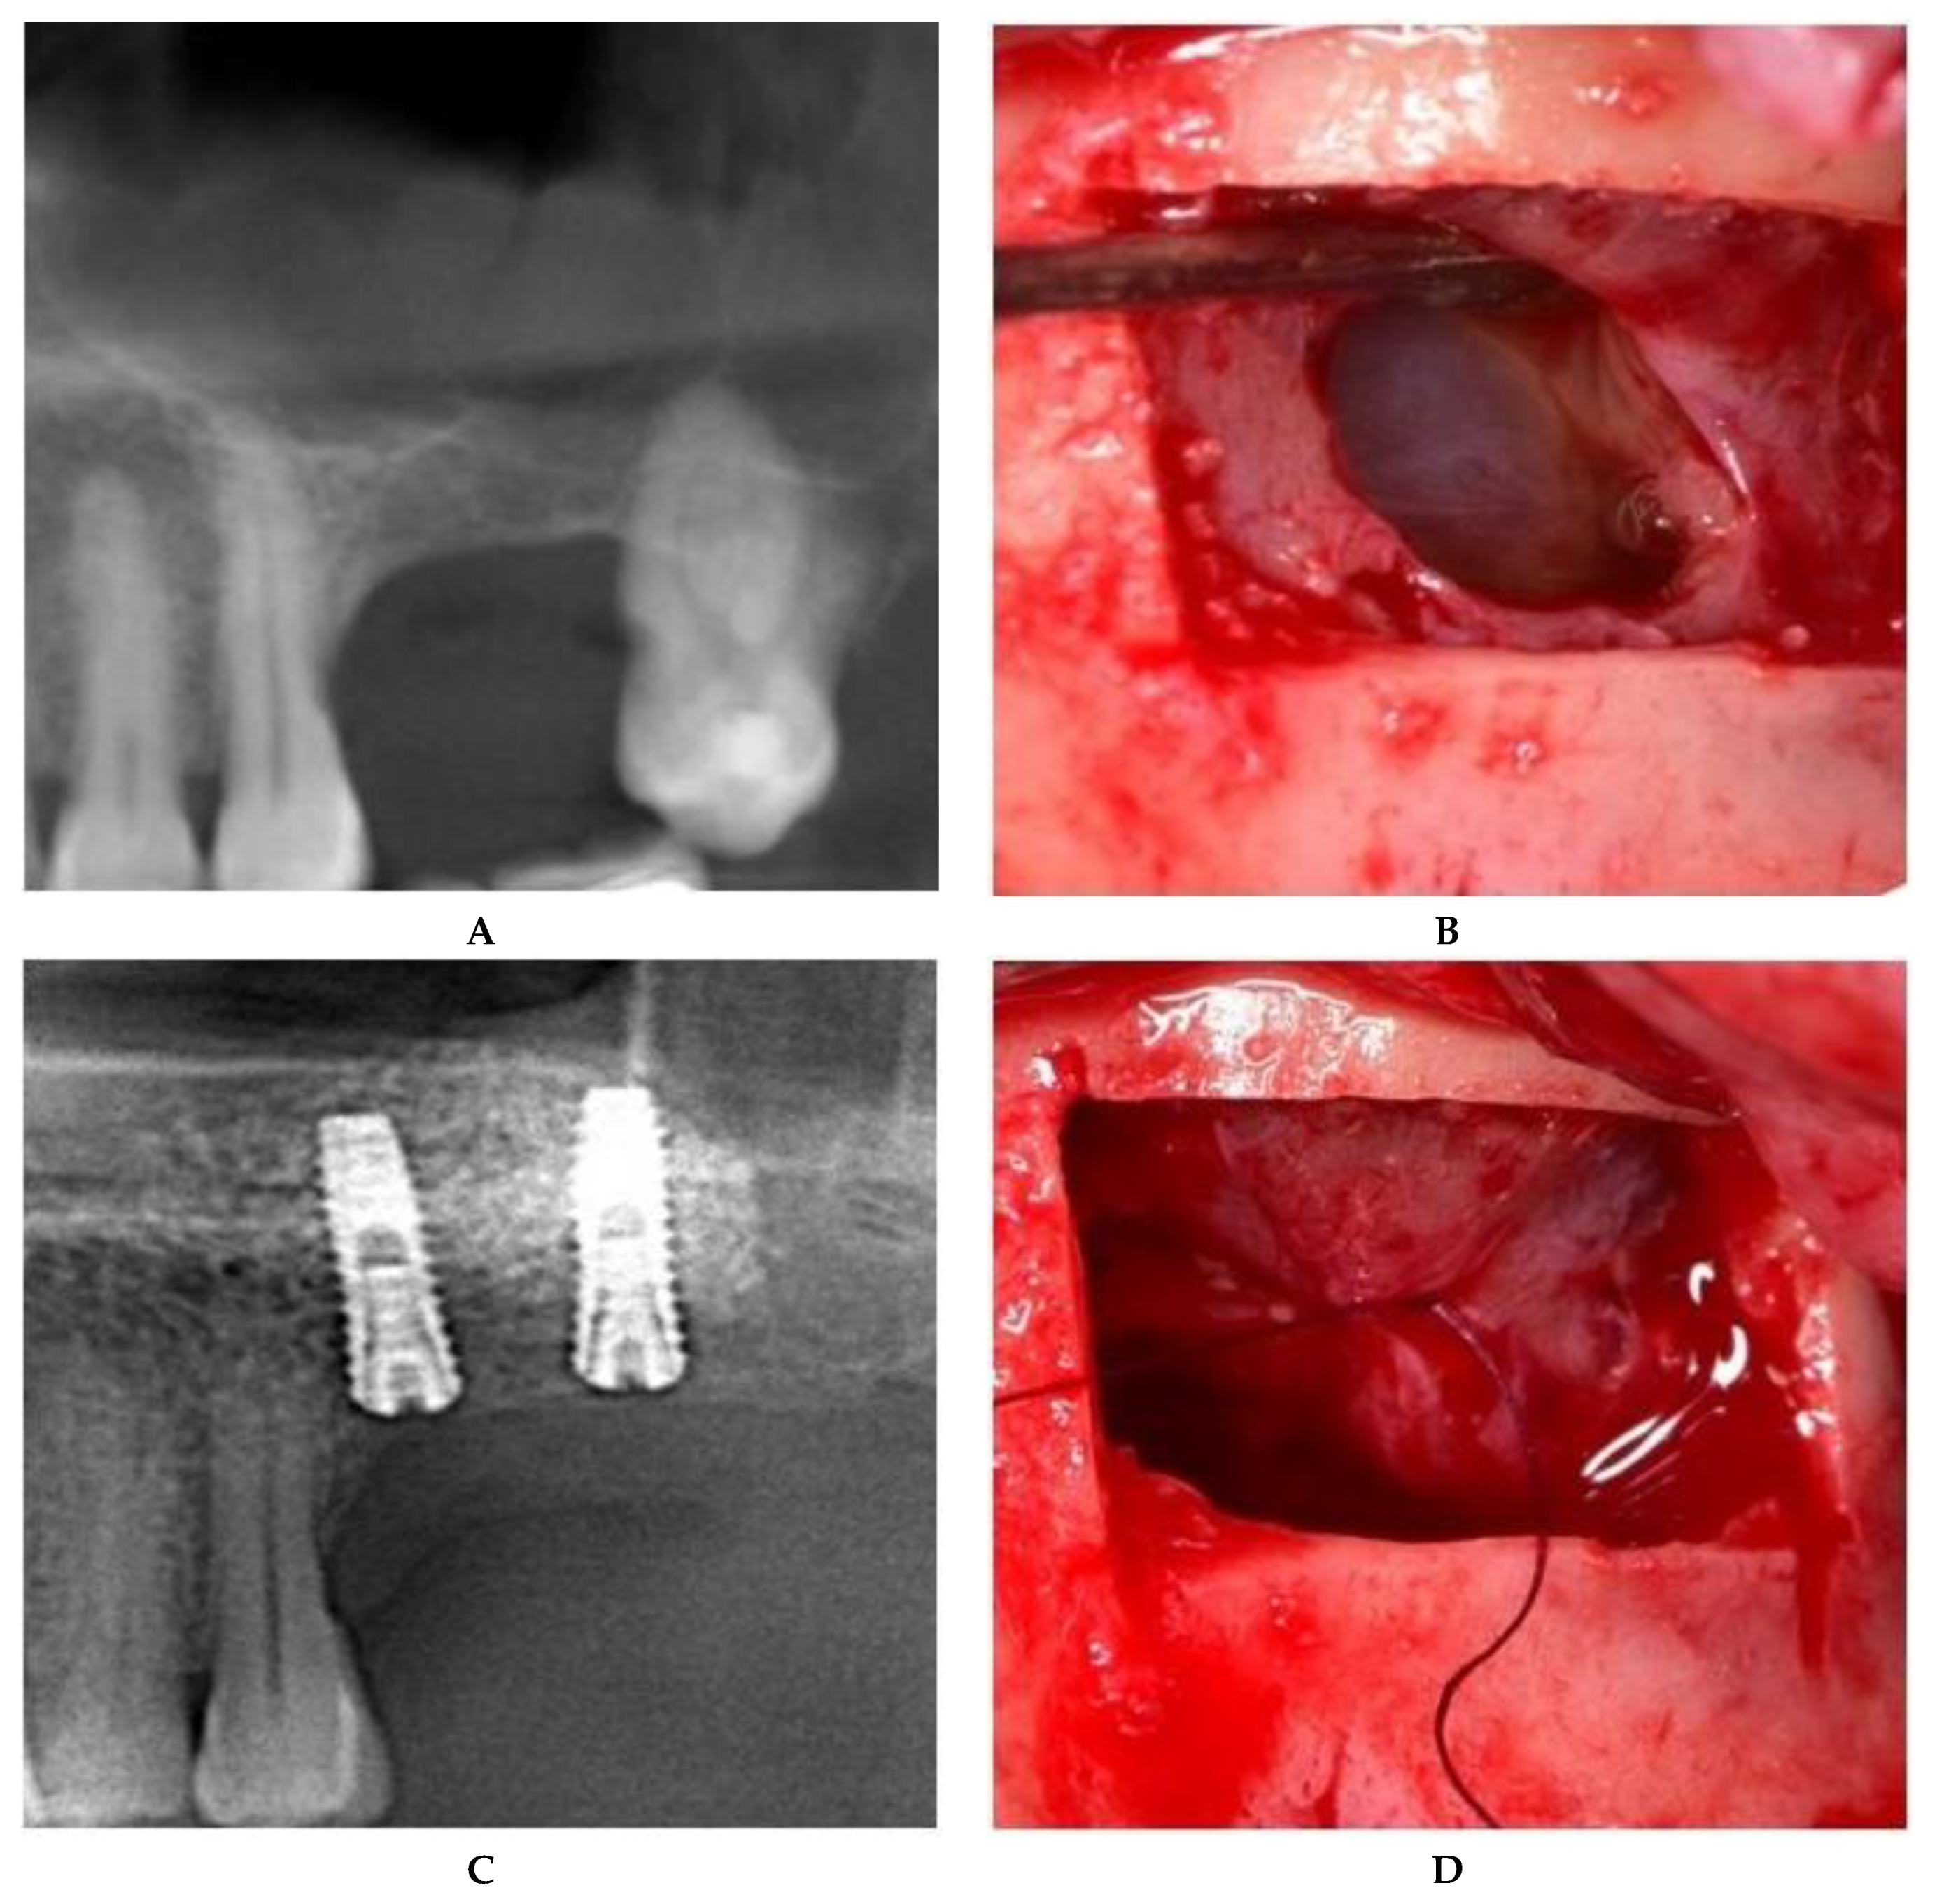

For large or multiple perforations, a single large pericardium membrane is placed in intimate contact on the elevated sinus membrane covering beyond the margin of the perforated area/s. In this study, collagen membranes with a low resorption rate (CopiOs Pericardium Membrane, Zimmer Biomet, Warsaw, IN, USA) were used to seal the perforated Schneiderian mucosa (Figure 1).

Schneiderian membrane sealing technique with collagen membrane coverage. (A) Preoperative CBCT image. (B) Large, multiple Schneiderian membrane perforations. (C) Bone graft placed in the collagen membrane “pouch”. (D) Postoperative CBCT after implant placement.

Large (more than 10 mm) or multiple perforations usually occur in thin, fragile sinus membranes with reduced elasticity. The remaining mucosal tissue between multiple perforations makes it impossible to suture without additional strain on the membrane. In addition, medially positioned perforations from the osteotomy contour lead to reduced access and visibility, which hindered correct suturing of the mucosal margins. For these reasons, the treatment of choice in this type of Schneiderian membrane tear is to seal with a pericardium membrane in order to provide an inside lining (Figure 1).